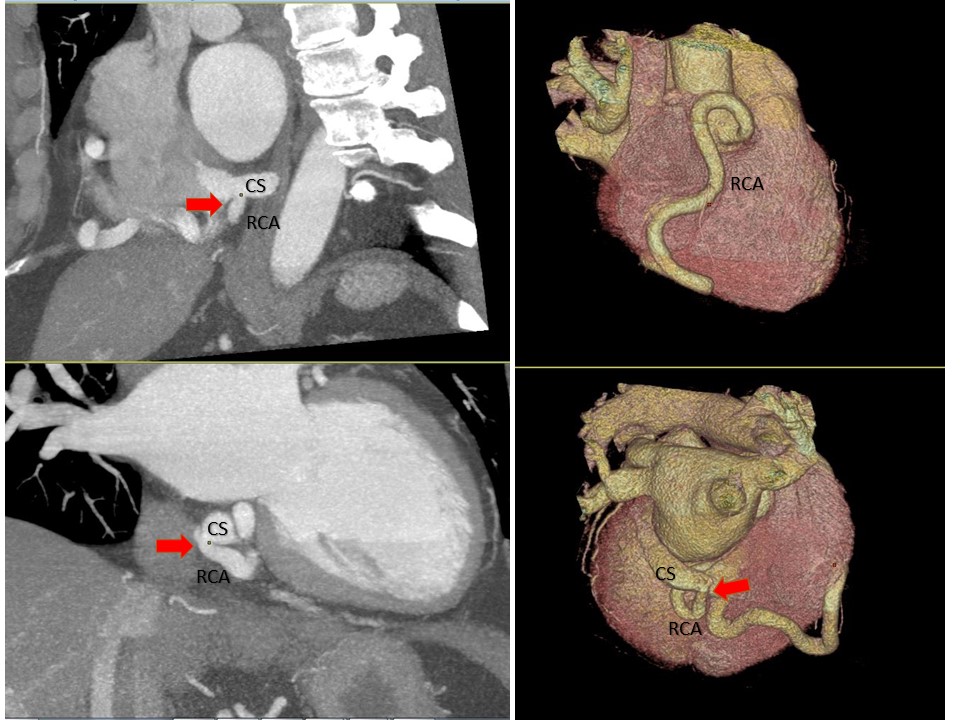

Nice case of #YesCCT RCA to coronary sinus (CS) fistula (red arrow) with giant tortuous RCA @Heart_SCCT @AChoiHeart @mmartinezheart @CardiacConsult @lillian_aldaia @LindaGillamMD